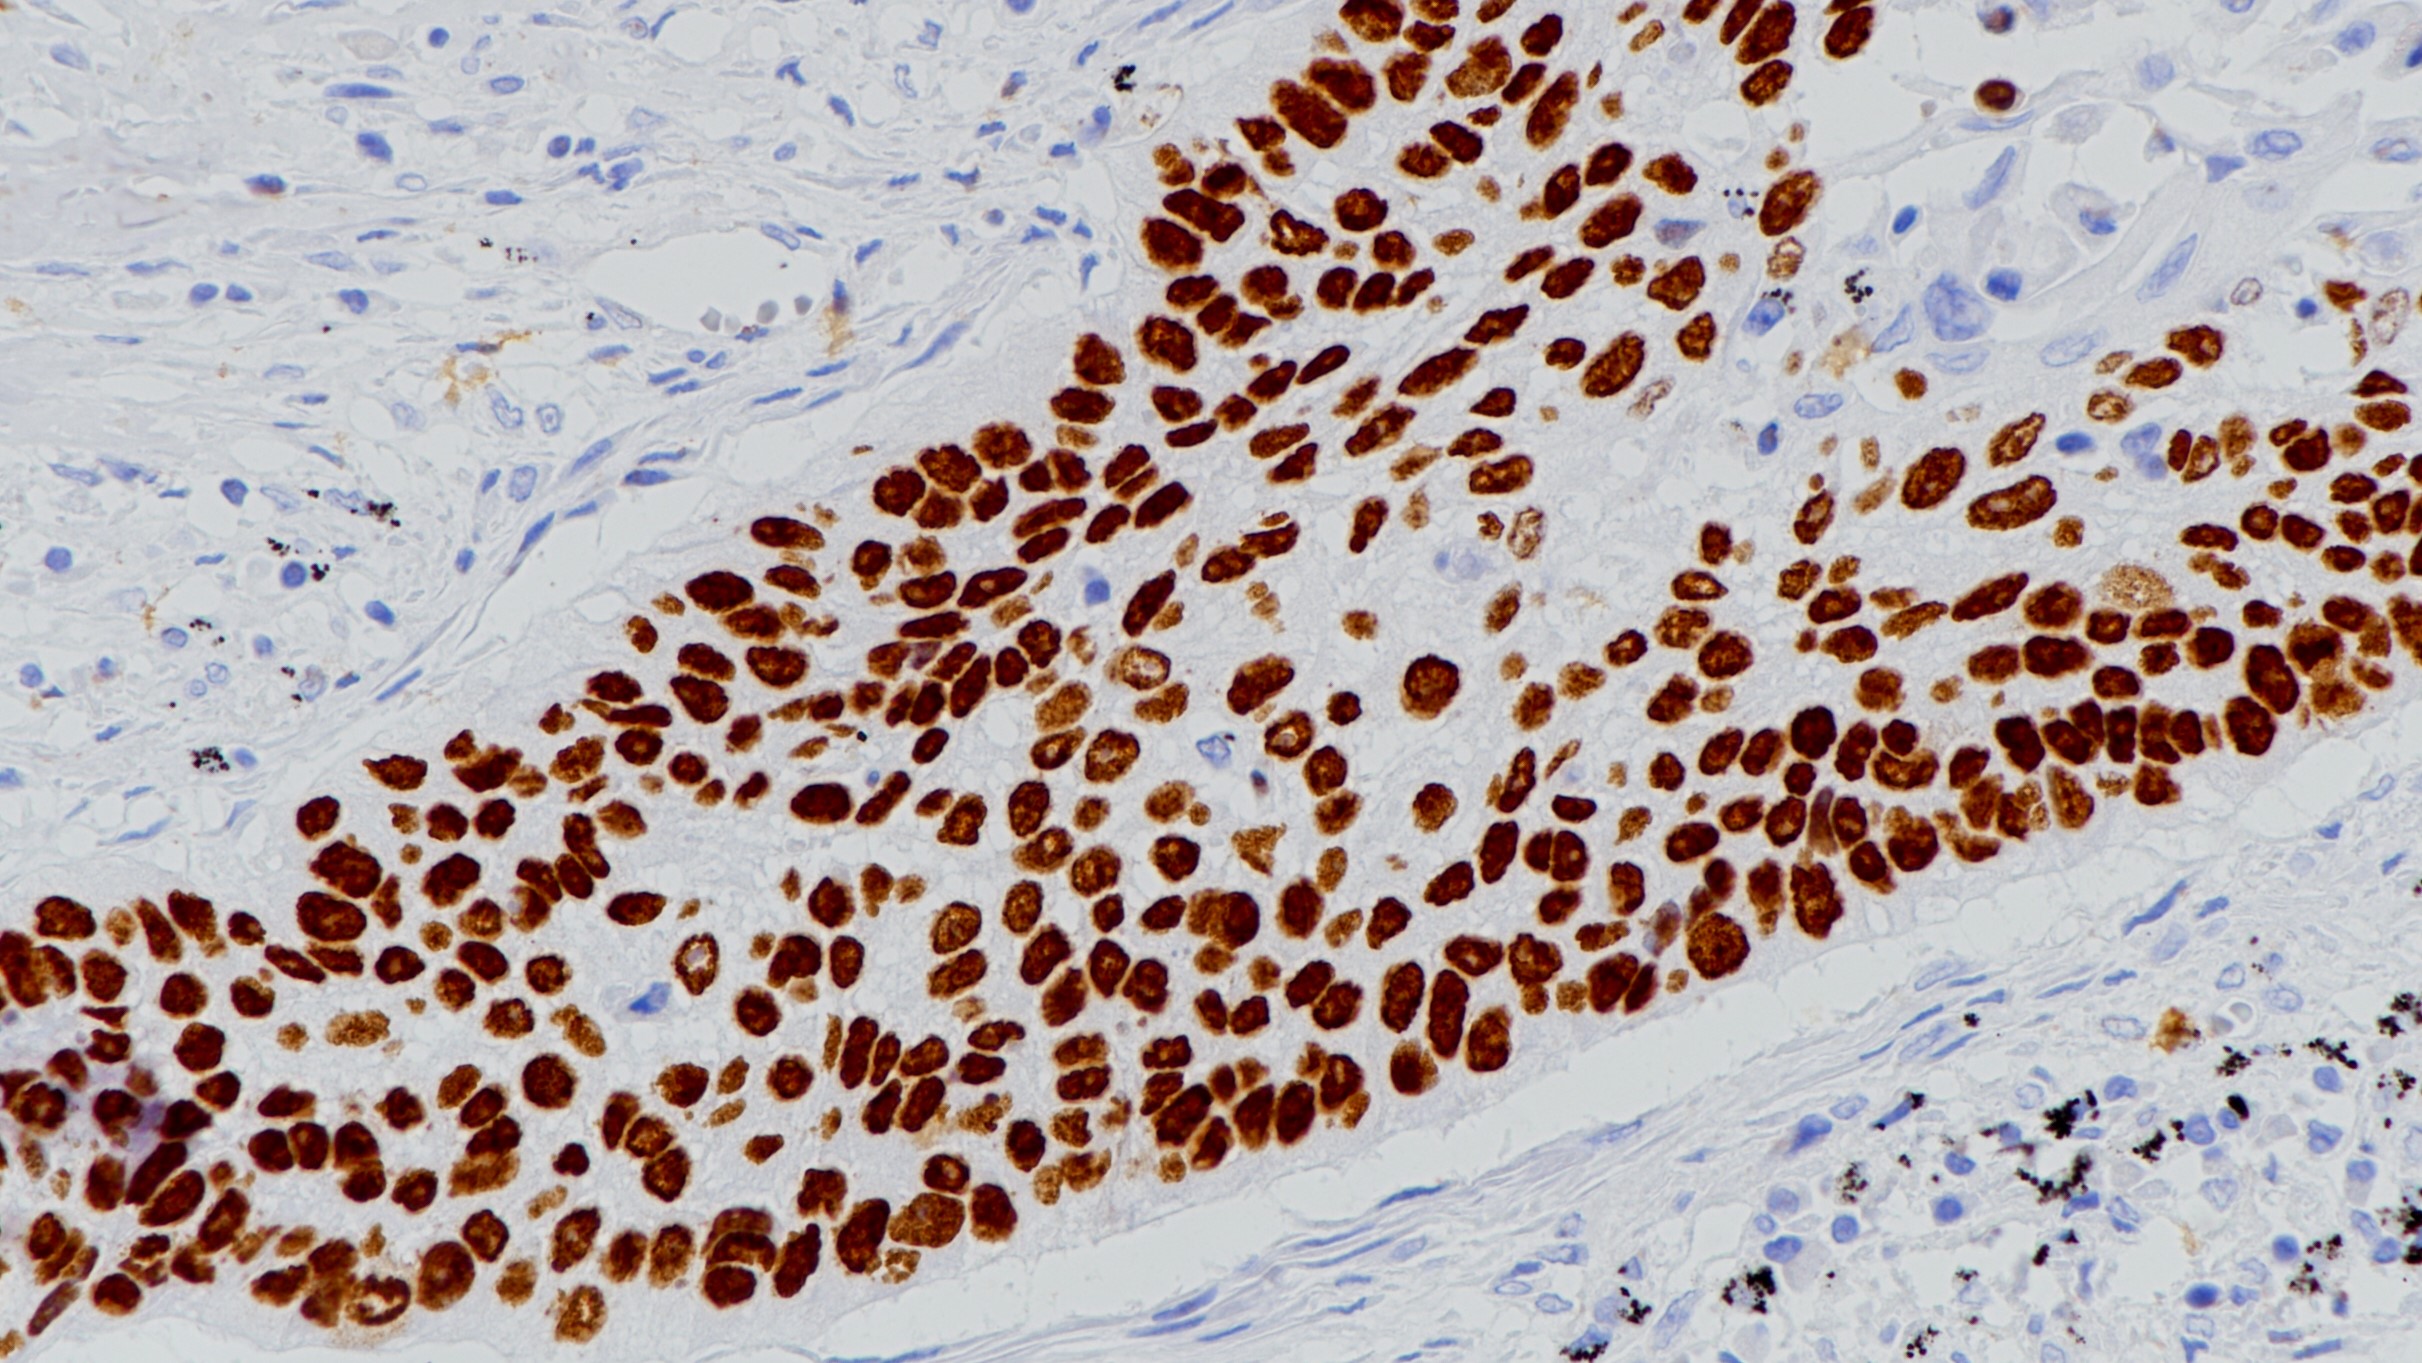

1.Ferdinandusse S, et al. Subcellular localization and physiological role of α-methylacyl-CoA racemase. J Lipid Res. 2000; 41:1890-6.

2.Xu J, et al. Identification of Differentially Expressed Genes in Human Prostate Cancer Using Subtraction and Microarray. Cancer Res. 2000; 60:1677-82.